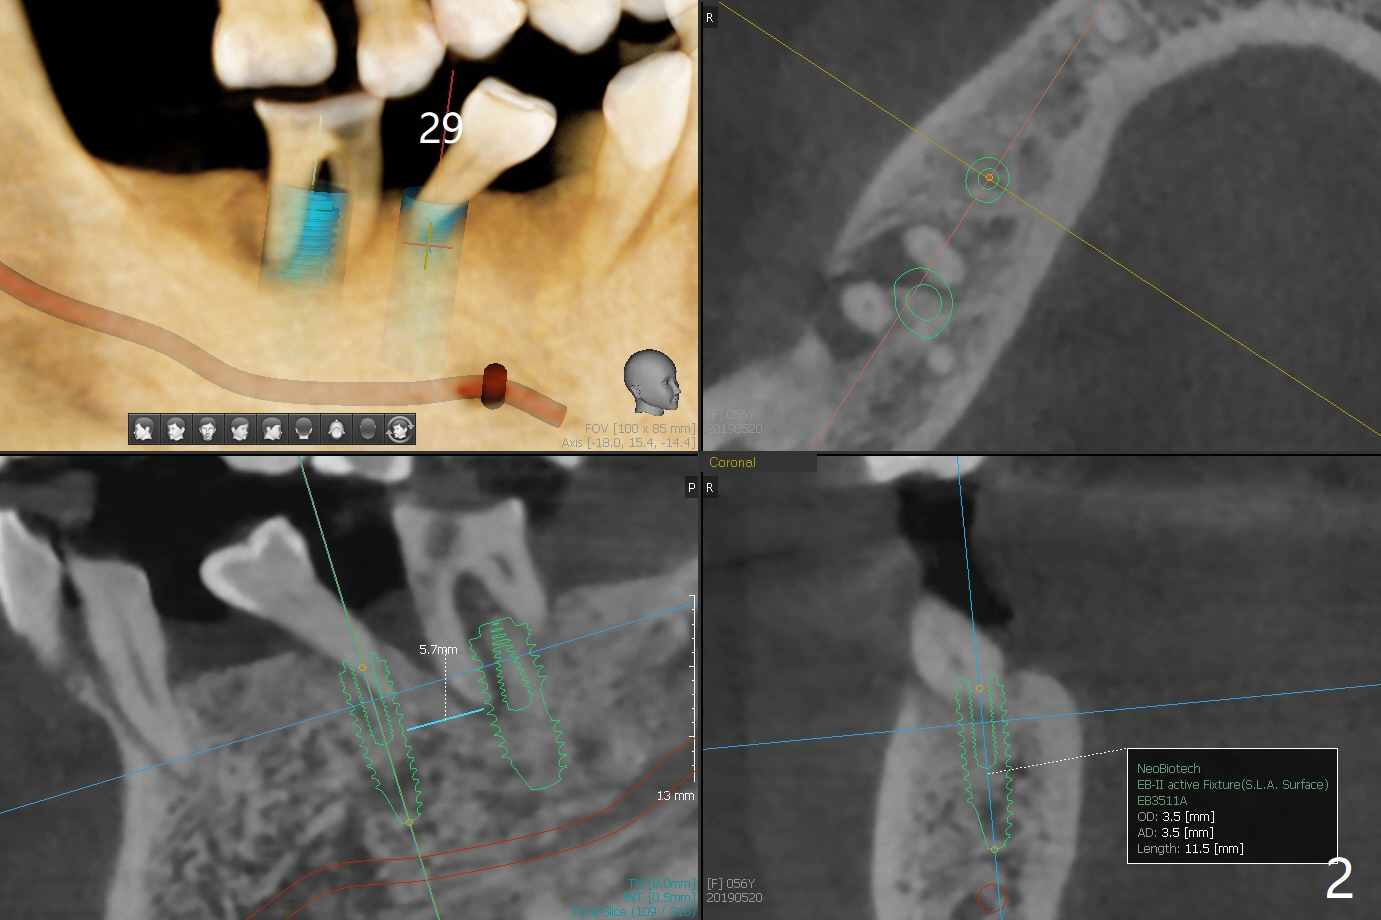

A 56-year-old woman does not want implant FPD at #18-20 six months post #18 and 20 implant placement. She agrees not to save the teeth #29 and 30 (Fig.1,2). An implant will be placed at #28 (Fig.3).